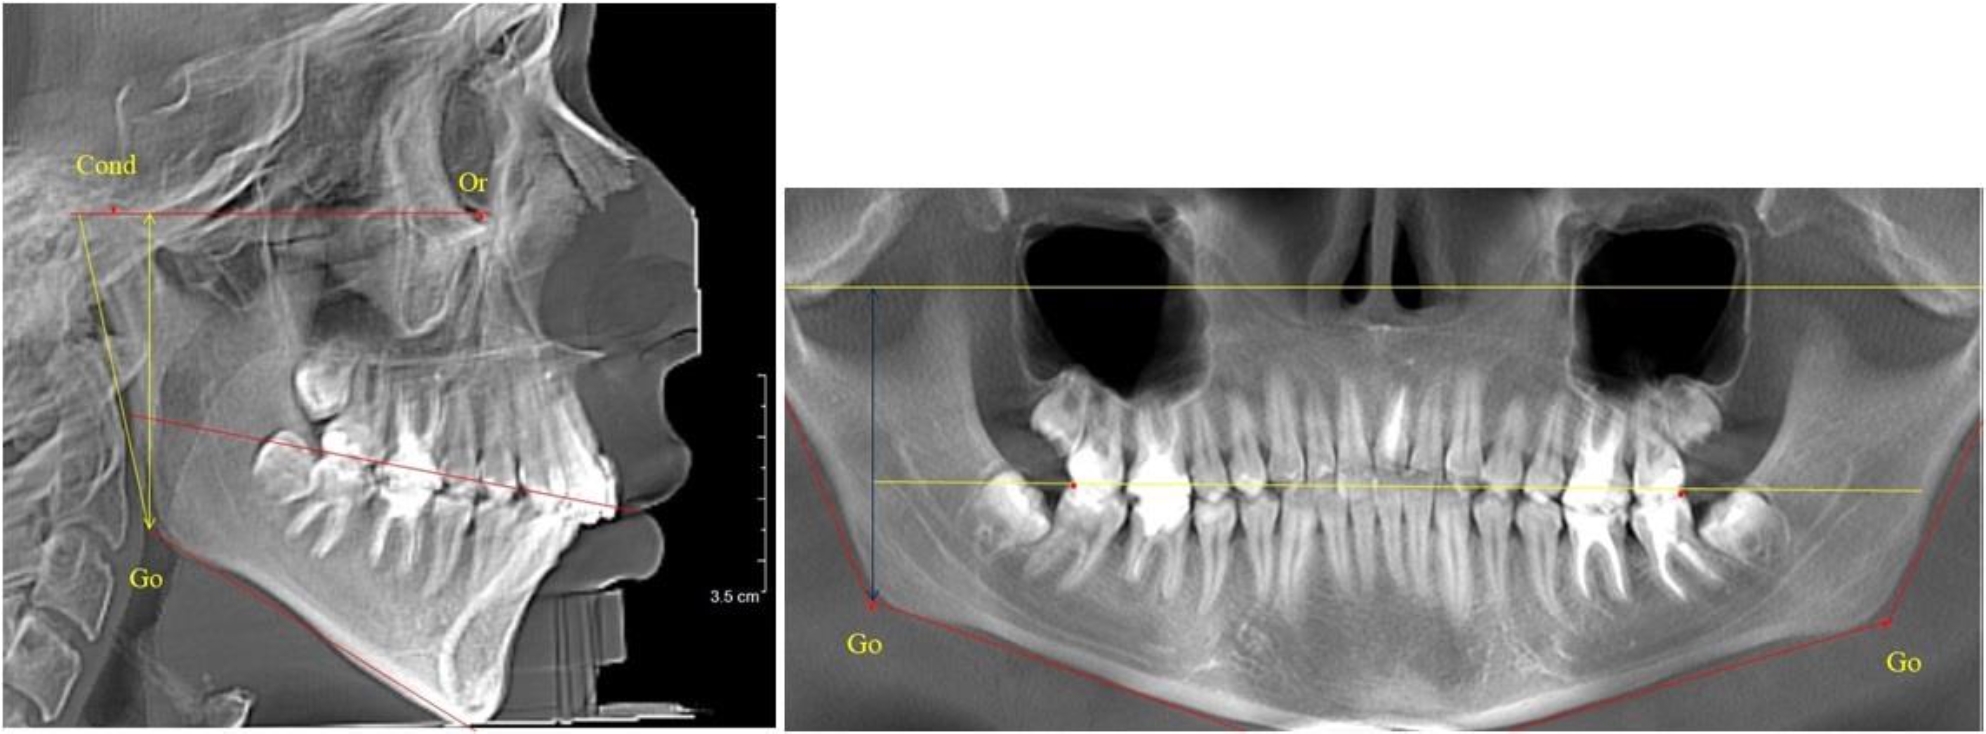

В 5-й группе были проанализированы 14 комплектов рентгенограмм, что составило (13,21 ± 3,29) % от общего числа. На всех рентгенограммах отмечен очередной этап подъема высоты прикуса, обусловленный прорезыванием вторых постоянных моляров. Окклюзионная линия делила ветвь на два отдела (рис. 5).

Рис. 5. ТРГ и ОПТГ пациента после смены молочных зубов и прорезывания вторых постоянных моляров

Высота ветви у детей 5-й группы составляла (62,87 ± 3,62) мм, что было достоверно больше, чем у детей других групп (р ˂ 0,05). При этом высота верхней окклюзионно-суставной части была (40,23 ± 2,01) мм, а нижней – (22,64 ± 1,78) мм. Высота верхней части была вдвое больше нижней, что и определяло особенности соразмерности частей ветви нижней челюсти в анализируемый возрастной период.

Относительные показатели соразмерности частей ветви нижней челюсти показали, что отношение высоты верхней части ветви к нижней в среднем составляло 1,78 ± 0,18. Отношение общей высоты ветви к верхней ее части составляло 1,56 ± 0,12, а отношение общей высоты ветви к нижней ее части было 2,78 ± 0,14, что и определяло особенности соразмерности частей ветви нижней челюсти в анализируемый возрастной период.